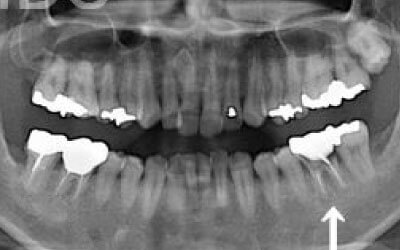

2 歯が傾いてくる、落ちてくる

歯はお互いに支え合ってバランスを保っています。つまり、歯が抜けるとその支えがなくなり、抜けた部分の隣の歯が傾いたり、上の歯が下にずれてくることがあります。